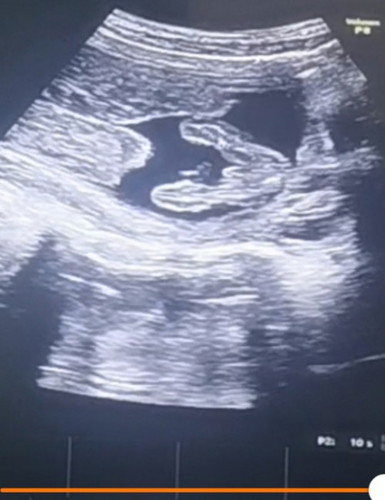

15wหมอบอกยังไม่ชัดค่ะบ้านนี้อยากได้ลูกสาวมีโอกาสจะเป็นลูกสาวบ้างไหมคะ

แม่จู๋ค่อนข้างชัดเจนเลยนะคะ😂